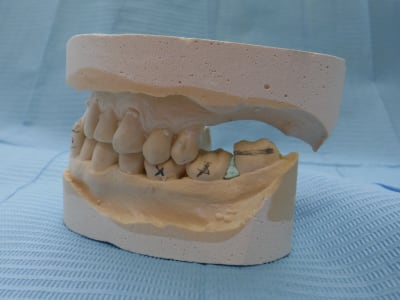

sans commentaire.

Ah si! 64 ans... et 41, 31 HS...